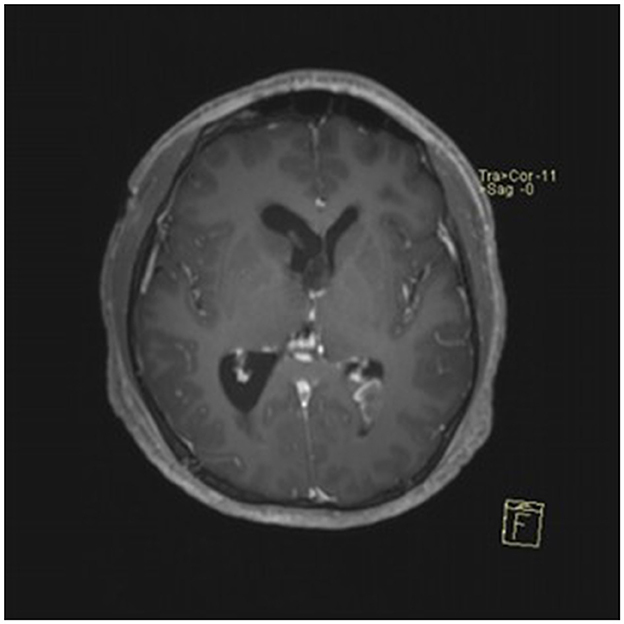

A 22-year-old male presented with intermittent dizziness and headache lasting for 2 weeks. MRI at admission revealed a cystic mass in the pineal region, accompanied by supratentorial hydrocephalus (Figures 3–5). No surgical contraindications were identified. After discussion with the patient's family, neuroendoscopic resection was performed via the Transfrontal-Transventricular-Transforaminal Approach. Intraoperatively, a 20 × 20 mm soft, well-vascularized tumor was found obstructing the cerebral aqueduct. The lesion had well-defined margins and was carefully dissected from surrounding adhesions, preserving adjacent veins and brain tissue. Macroscopic total resection was achieved en bloc (Figures 6–8). Postoperative day 1 MRI confirmed complete tumor removal and resolution of hydrocephalus (Figures 9–11). Postoperatively, no complications were observed. However, due to personal reasons, the patient was discharged on postoperative day 11. Histopathology confirmed a mixed germinoma. No recurrence or surgery-related complications were noted during follow-up.

Figure 3

Preoperative contrast-enhanced MRI (axial view) showing a cystic-solid mass in the pineal region with supratentorial hydrocephalus.

Figure 4